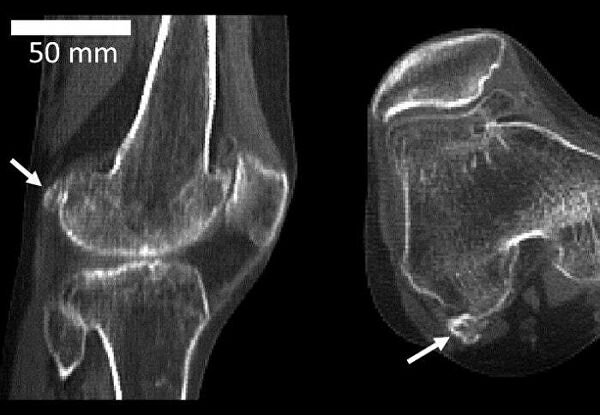

Подпорка для колена

Миллионы лет назад, на заре становления человеческого вида, из колена исчезла за ненадобностью маленькая косточка — флабелла. В последнее время ее снова начали находить.

Флабелла — одна из сесамовидных костей, располагающихся в сухожилиях. У животных она сформировалась примерно двести миллионов лет назад, чтобы придать прочности суставам, защитить сухожилие от повреждения при сильных нагрузках. Считается, что у человека эта кость повышает механическое сопротивление икроножной мышцы. Но зачем это нужно?

Ученые из Имперского колледжа Лондона (Великобритания) проанализировали 66 научных работ начиная с 1875 года, содержащих сведения о флабелле. Выяснилось, что она встречается в 36,8 процента случаев чаще у азиатов, жителей Океании и Южной Америки, а если брать в расчет половой признак, то предпочтительнее у мужчин. В целом в 2018 году эта кость распространена в человеческой популяции в 3,5 раза чаще, чем век назад — в 1918-м.Рост флабеллы обусловлен генетически, но вот ее окостенение у всех происходит в разном возрасте и, возможно, зависит от механических причин. Чаще ее встречают у людей после 70 лет, но она может проявиться уже у 12-летних.Обычно флабелла появляется в обеих коленях и служит причиной осложнений после хирургических операций по замене суставов. В имплантате ее присутствие не учитывают, и это вызывает боль при ходьбе. В итоге «лишнюю» кость приходится удалять.Замечено также, что у людей с флабеллой нередко встречаются некоторые нейропатические заболевания, а риск остеоартрита колена увеличивается в два раза. Но что причина, а что следствие, пока неясно.

Флаббела — крошечная кость в колене — стала появляться у людей все чаще за последние 150 лет